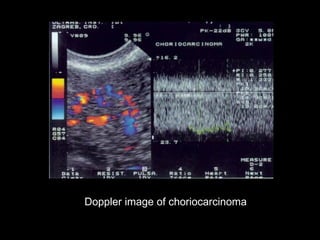

Doppler image of choriocarcinoma

Doppler image ofchoriocarcinoma